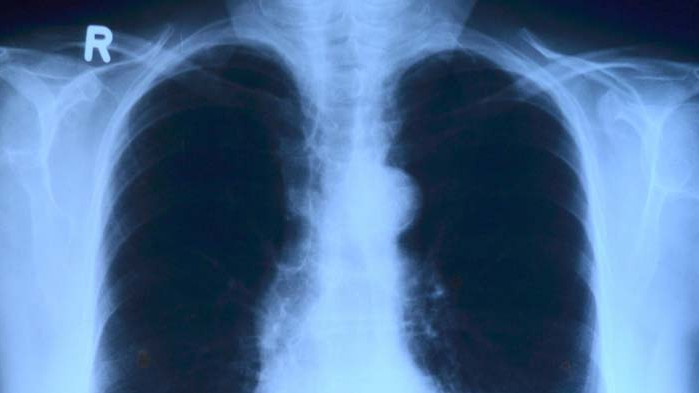

Проф. Галина Кирова: Пълното възстановяване на белия дроб след Ковид е след третия месец

По думите ѝ, ако човек е оздравял след тежко преболедуване от COVID-19, пълното възстановяване на белия дроб е след третия месец. Тя посъветва да не се бърза за рентгенова снимка.